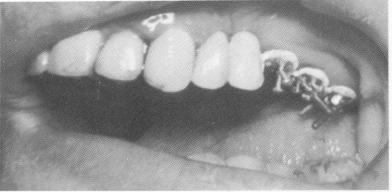

Fig. 13-53. A, The bridge with the scalloped template was fitted into position. B and C, The prosthesis was cemented with hard cement.